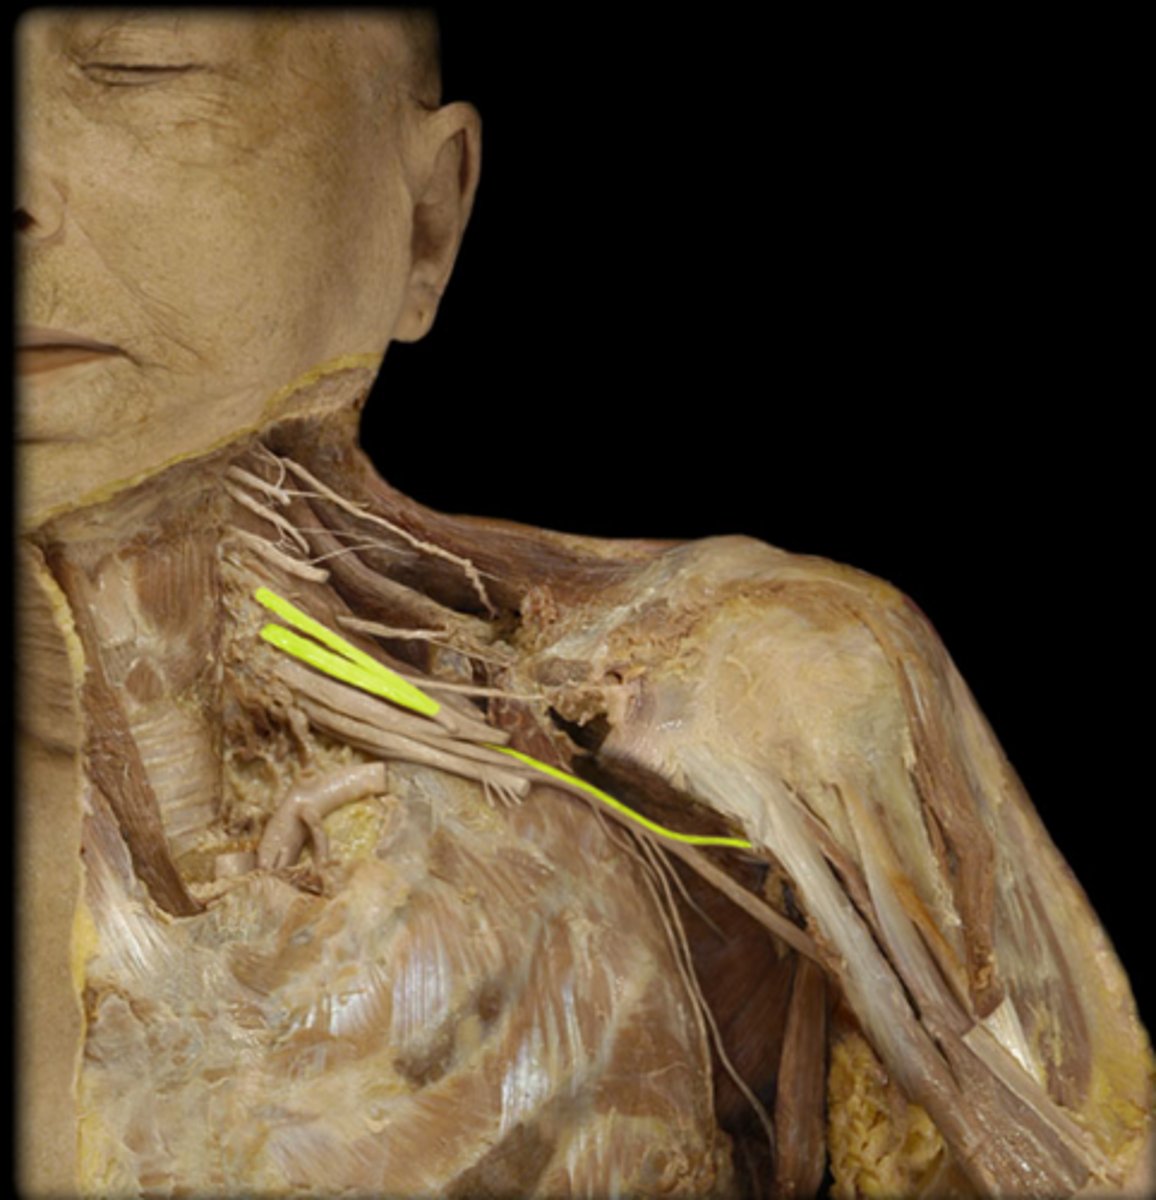

Musculocutaneous n.

coracobrachialis, biceps brachii, and brachialis muscles

Median n.

Name this structure.

Ulnar n.

medial aspect (pinky side) of the forearm